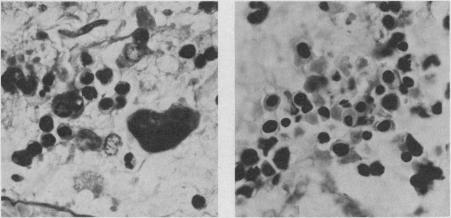

A 58-year-old woman presented with pericarditis and pericardial effusion. Investigation revealed that she was suffering from a thrombocythemic myeloproliferative disorder; she died of massive pulmonary embolism 10 days after admission. Histologic study verified epicardial and pericardial trilineage hematopoiesis. Pericarditis is an unusual feature of essential thrombocythemia and it may occur in direct relation to the abnormal cellular proliferation.

一名58岁女性因心包炎和心包积液就诊。检查发现她患有血小板增多性骨髓增殖性疾病;入院10天后死于大面积肺栓塞。组织学研究证实心外膜和心包存在三系造血。心包炎是原发性血小板增多症的一个不寻常特征,可能与异常细胞增殖直接相关。